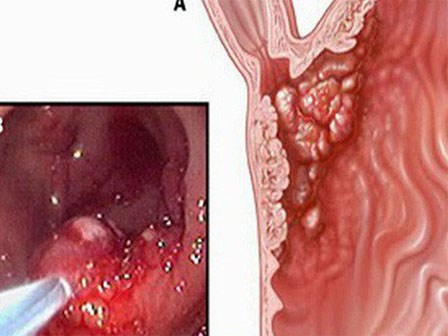

Căn bệnh ung thư xếp hàng thứ tư ở Việt Nam - thủ phạm liên quan chặt chẽ tới dinh dưỡng

Bộ Y tế mới đây đã đưa ra phác đồ điều trị mới cho bệnh ung thư đại trực tràng - căn bệnh ung thư có tỷ lệ mắc đang gia tăng tại nước ta.

Nguyên PGĐ Bệnh viện K: Loại ung thư di truyền nhiều nhất, cần tầm soát sớm kẻo muộn

Chuyên gia khuyến cáo ung thư đại trực tràng có yếu tố gia đình cần được nhận diện điều trị trước 30 tuổi và chậm nhất 35 tuổi để giảm thiểu rủi ro.